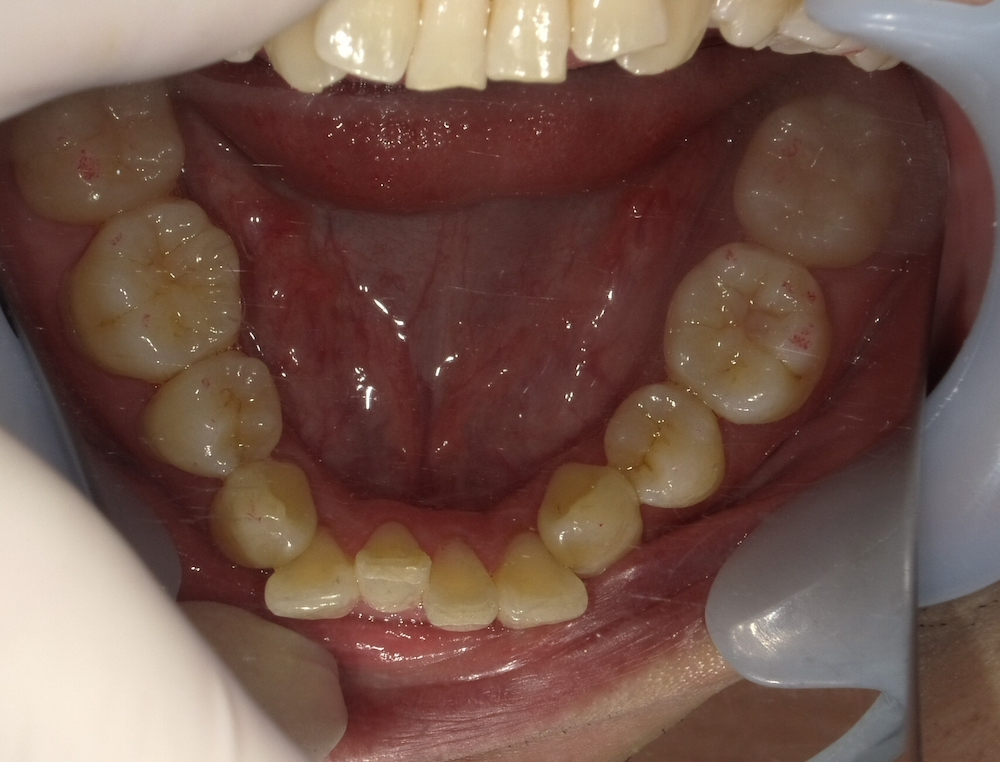

Before

症例3 20年前に上下4本の小臼歯を抜歯して矯正後、保定装置を中断してしまったケース(重度)

- 治療方法:インビザライン上下

- 治療期間:1年3ヶ月

- 治療費用 :¥990000

- 治療のリスク・デメリット: 歯肉退縮・ブラックトライアングル